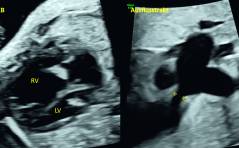

Sonoquiz: Was ist das?

Die Patientin wird erstmals zugewiesen in der 33. Woche wegen auffälligem Herzen. PDF Dokument

Auflösung Sonoquiz: Arthrogryposis multiplex congentia (AMC) bei Escobar Syndrom

Arthrogryposis multiplex congenita ist eine klinische Entität, welche das Vorhandensein von mindestens zwei Kontrakturen an mindestens zwei Gelenken voraussetzt. PDF Dokument